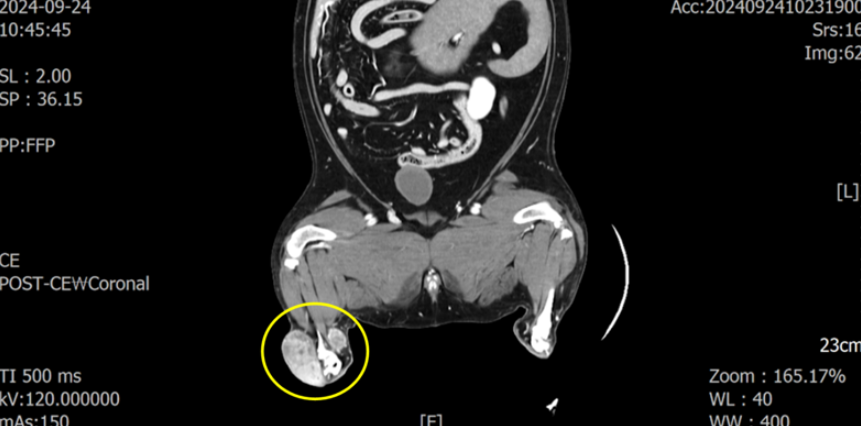

CT 촬영을 통해 해당 종양이 아킬레스건 주변을 둘러싸고 근육 침습도 일으키고 있는 양상을 확인하였습니다.

원격 전이를 의심할 만한 소견은 없었지만 인접한 림프절 중 하나인 sublumbar LN(요추하 림프절이 커져 있었습니다.